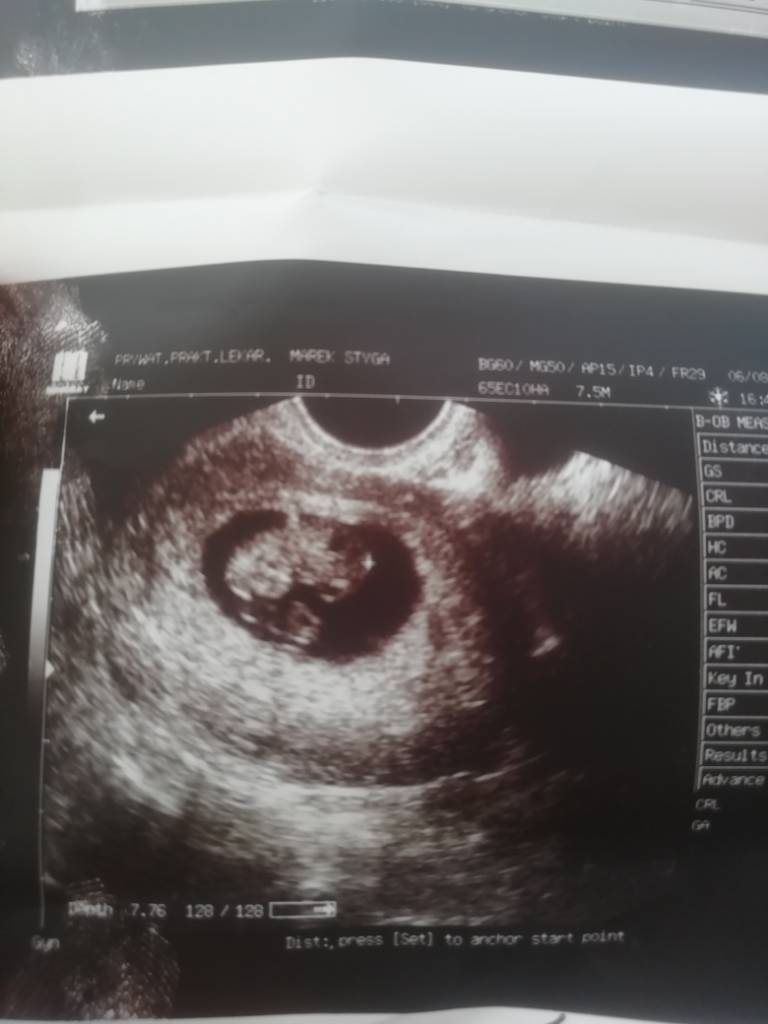

19.06 z usg wychodzi na 31.03 a z miesiączki na 25.03To moja fasolka:

Zobacz załącznik 1006921

Malo widac, dlatego czekam na drugi scan, 26 sierpnia.